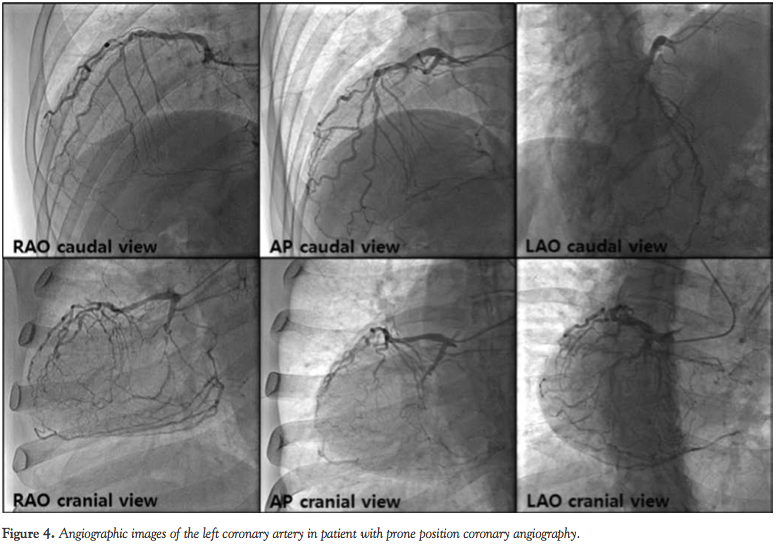

catheter revealed total occlusion of the proximal RCA (Figure 3). Coronary angiography with a 5 Fr Judkins left catheter revealed diffuse 50%-60% luminal narrowing of the proximal to distal left anterior descending coronary artery (LAD) and total occlusion of the proximal left circumflex coronary artery (LCX) with collateral flows from distal LAD and septal branches to posterior descending and posterolateral branches of the RCA (Figure 4).

In our case, prone position coronary angiography was performed without difficulty. In addition, interpretation of prone position coronary angiography was simply done since only the cranial and caudal views were opposite compared to conventional supine position angiography. These consequences may be due to the geometry of the heart as well as the coronary anatomy, which were neither parallel nor perpendicular to the patient’s position. Although we did not undergo percutaneous coronary intervention (PCI) since it was not feasible to achieve complete revascularization, performing prone position PCI would not be troublesome compared to conventional supine position PCI.